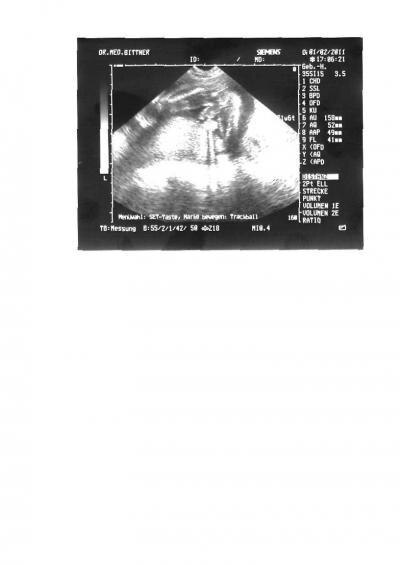

Bitte helft uns...auf dem Foto soll es laut FA auf dem Kopf gedreht sein..mit dem Rücken auf die rechte Seite gedreht und mit dem Po nach oben....Wer kann was erkennen?? Wir erkennen leider gar nix...

Bild zu Hiiilllffee wer kann uns helfen?? FA verriet nicht was es wird..Mädchen o. Junge - Forum für Juni - Mamis

Ich kann erkennen wie das Baby liegt ect aber das geschlecht nicht

ein vorsichtiger Tip: Junge.... ich meine die Hoden und den Penis zu sehen.